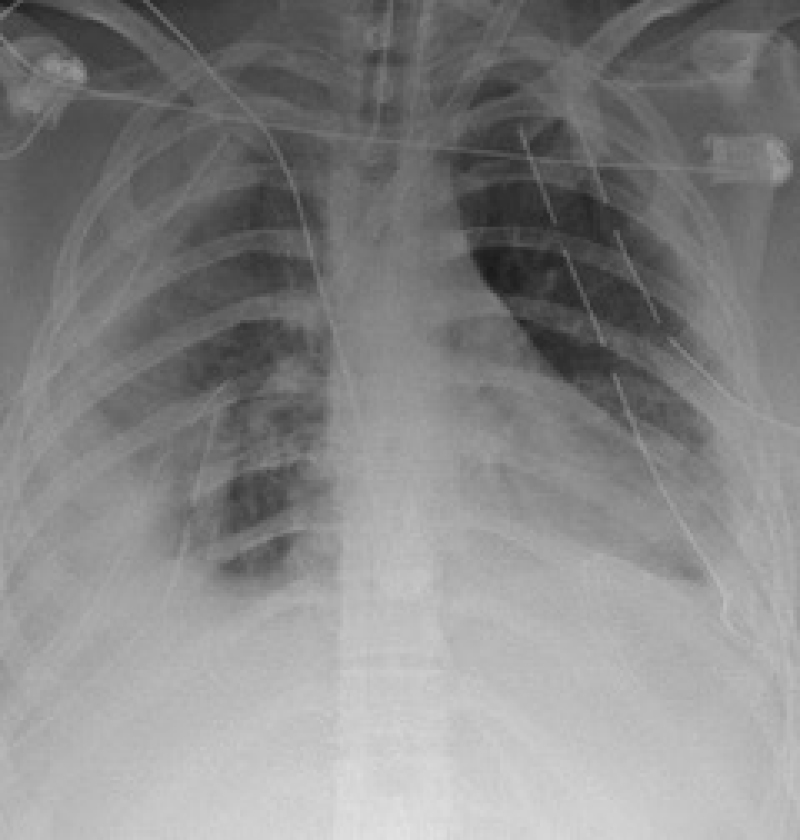

She remained on ECMO for the next nine days and during this time she underwent two separate thoracic procedures: A left video-assisted thoracoscopic surgery (VATS) exploration and washout, and a subsequent right VATS exploration and washout. During both of these procedures complex pleural collections were broken down and evacuated. Repeat chest radiograph demonstrated a substantial improvement in the appearance of the lung fields (Figure 4).

Figure 4: Chest radiograph showing a marked improvement. View Figure 4